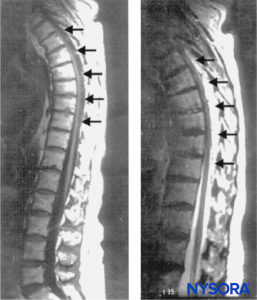

The dorsal venous plexus is the most commonly implicated source of hemorrhage because this plexus lacks valves and permits reversal in blood flow during increased intravascular pressure from physical activity. These veins lack protection as they are surrounded only by loose areolar tissue and are therefore vulnerable to sudden increases in intra-abdominal or intrathoracic pressure, leading to rupture and hemorrhage. The epidural venous plexus is most prominent in the thoracic spine, and spontaneous SEH most often occurs in the thoracic and cervicothoracic region, followed by the thoracolumbar area. SEH is typically posterior or posterolateral to the thecal sac (Figure 1) because the firm adherence of the dural sac to the posterior longitudinal ligament in the ventral aspect of the spinal canal prevents the accumulation of hematoma. The dorsal aspect of the thoracic or lumbar region is commonly involved, and expansion is typically limited to only a few vertebral levels.

FIGURE 1. Sagittal magnetic resonance images of the thoracolumbar spine. A large complex epidural hematoma extending from T3 to T10 through T11 is seen with hypo- and isodense signal characteristics on a T1-weighted image (left; arrows) and hyperintense signal characteristics on a T2-weighted image (right; arrows). At the center of the hematoma, the spinal cord abuts the posterior aspect of the thoracic vertebral

Rapid radiologic evaluation is essential to minimize delay in treatment of SEH. Currently, magnetic resonance imaging (MRI) is the diagnostic imaging method of choice for spinal emergencies because it allows rapid, noninvasive evaluation of the vertebral column and the spinal cord in all planes. Spinal MRI may delineate the location of an epidural hematoma and identify an associated vascular malformation; it will also provide information regarding the extent of the hematoma as well as the degree of cord compression. MRI can also aid in assessment of the age of the hematoma (Figure 1).

The chronologic characteristics of an MRI of SEH are similar to those seen with intracranial hemorrhage. In the hyperacute stage (first 6 hours), the SEH appears isointense compared to the spinal cord on T1-weighted images and mildly hyperintense and heterogeneous on T2-weighted images, as a result of the presence of intracellular oxyhemoglobin. In the acute stage (7–72 hours), the hematoma is still isointense on T1-weighted images and becomes hypointense on T2-weighted images. This is due to the presence of intracellular deoxyhemoglobin, which causes T2 shortening. As the concentration of methemoglobin increases, the hematoma becomes hyperintense and homogeneous on T1- and T2-weighted images. Gadolinium-enhanced magnetic resonance arteriography (MRA) may further define the extent of an arteriovenous malformation.